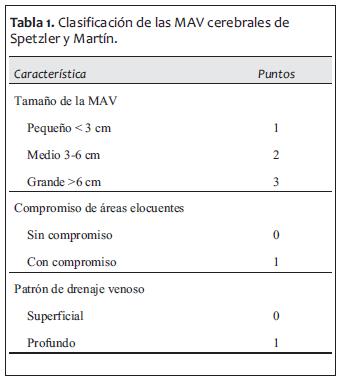

Según la clasificación de Spetzler y Martín se dividen en cinco grados de acuerdo al tamaño, el compromiso de áreas cerebrales elocuentes y el patrón de drenaje venoso (tabla 1).